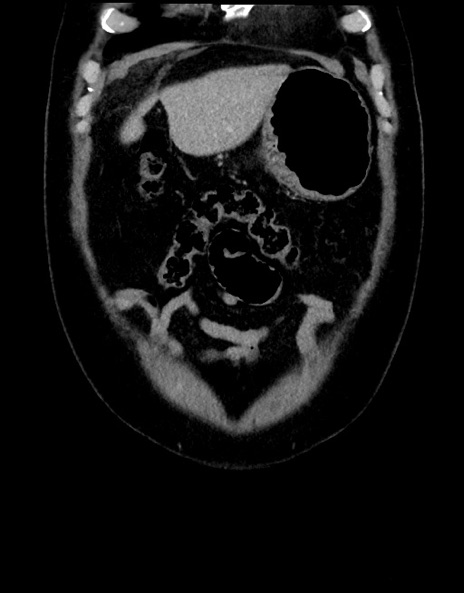

横断像

症例15(冠状断像)

【症例】70歳代男性

【主訴】腹痛

【現病歴】今朝から腹痛あり。全体的に痛い。特に左上の方。排ガスが今日はない。冷や汗が出る。

【既往歴】直腸癌術後

【身体所見】左側腹部〜上腹部に圧痛あり。腹膜刺激症状明らかなではない。軽度反跳痛。左下腹部に術後瘢痕あり。

【データ】WBC 7700、CRP 0.02